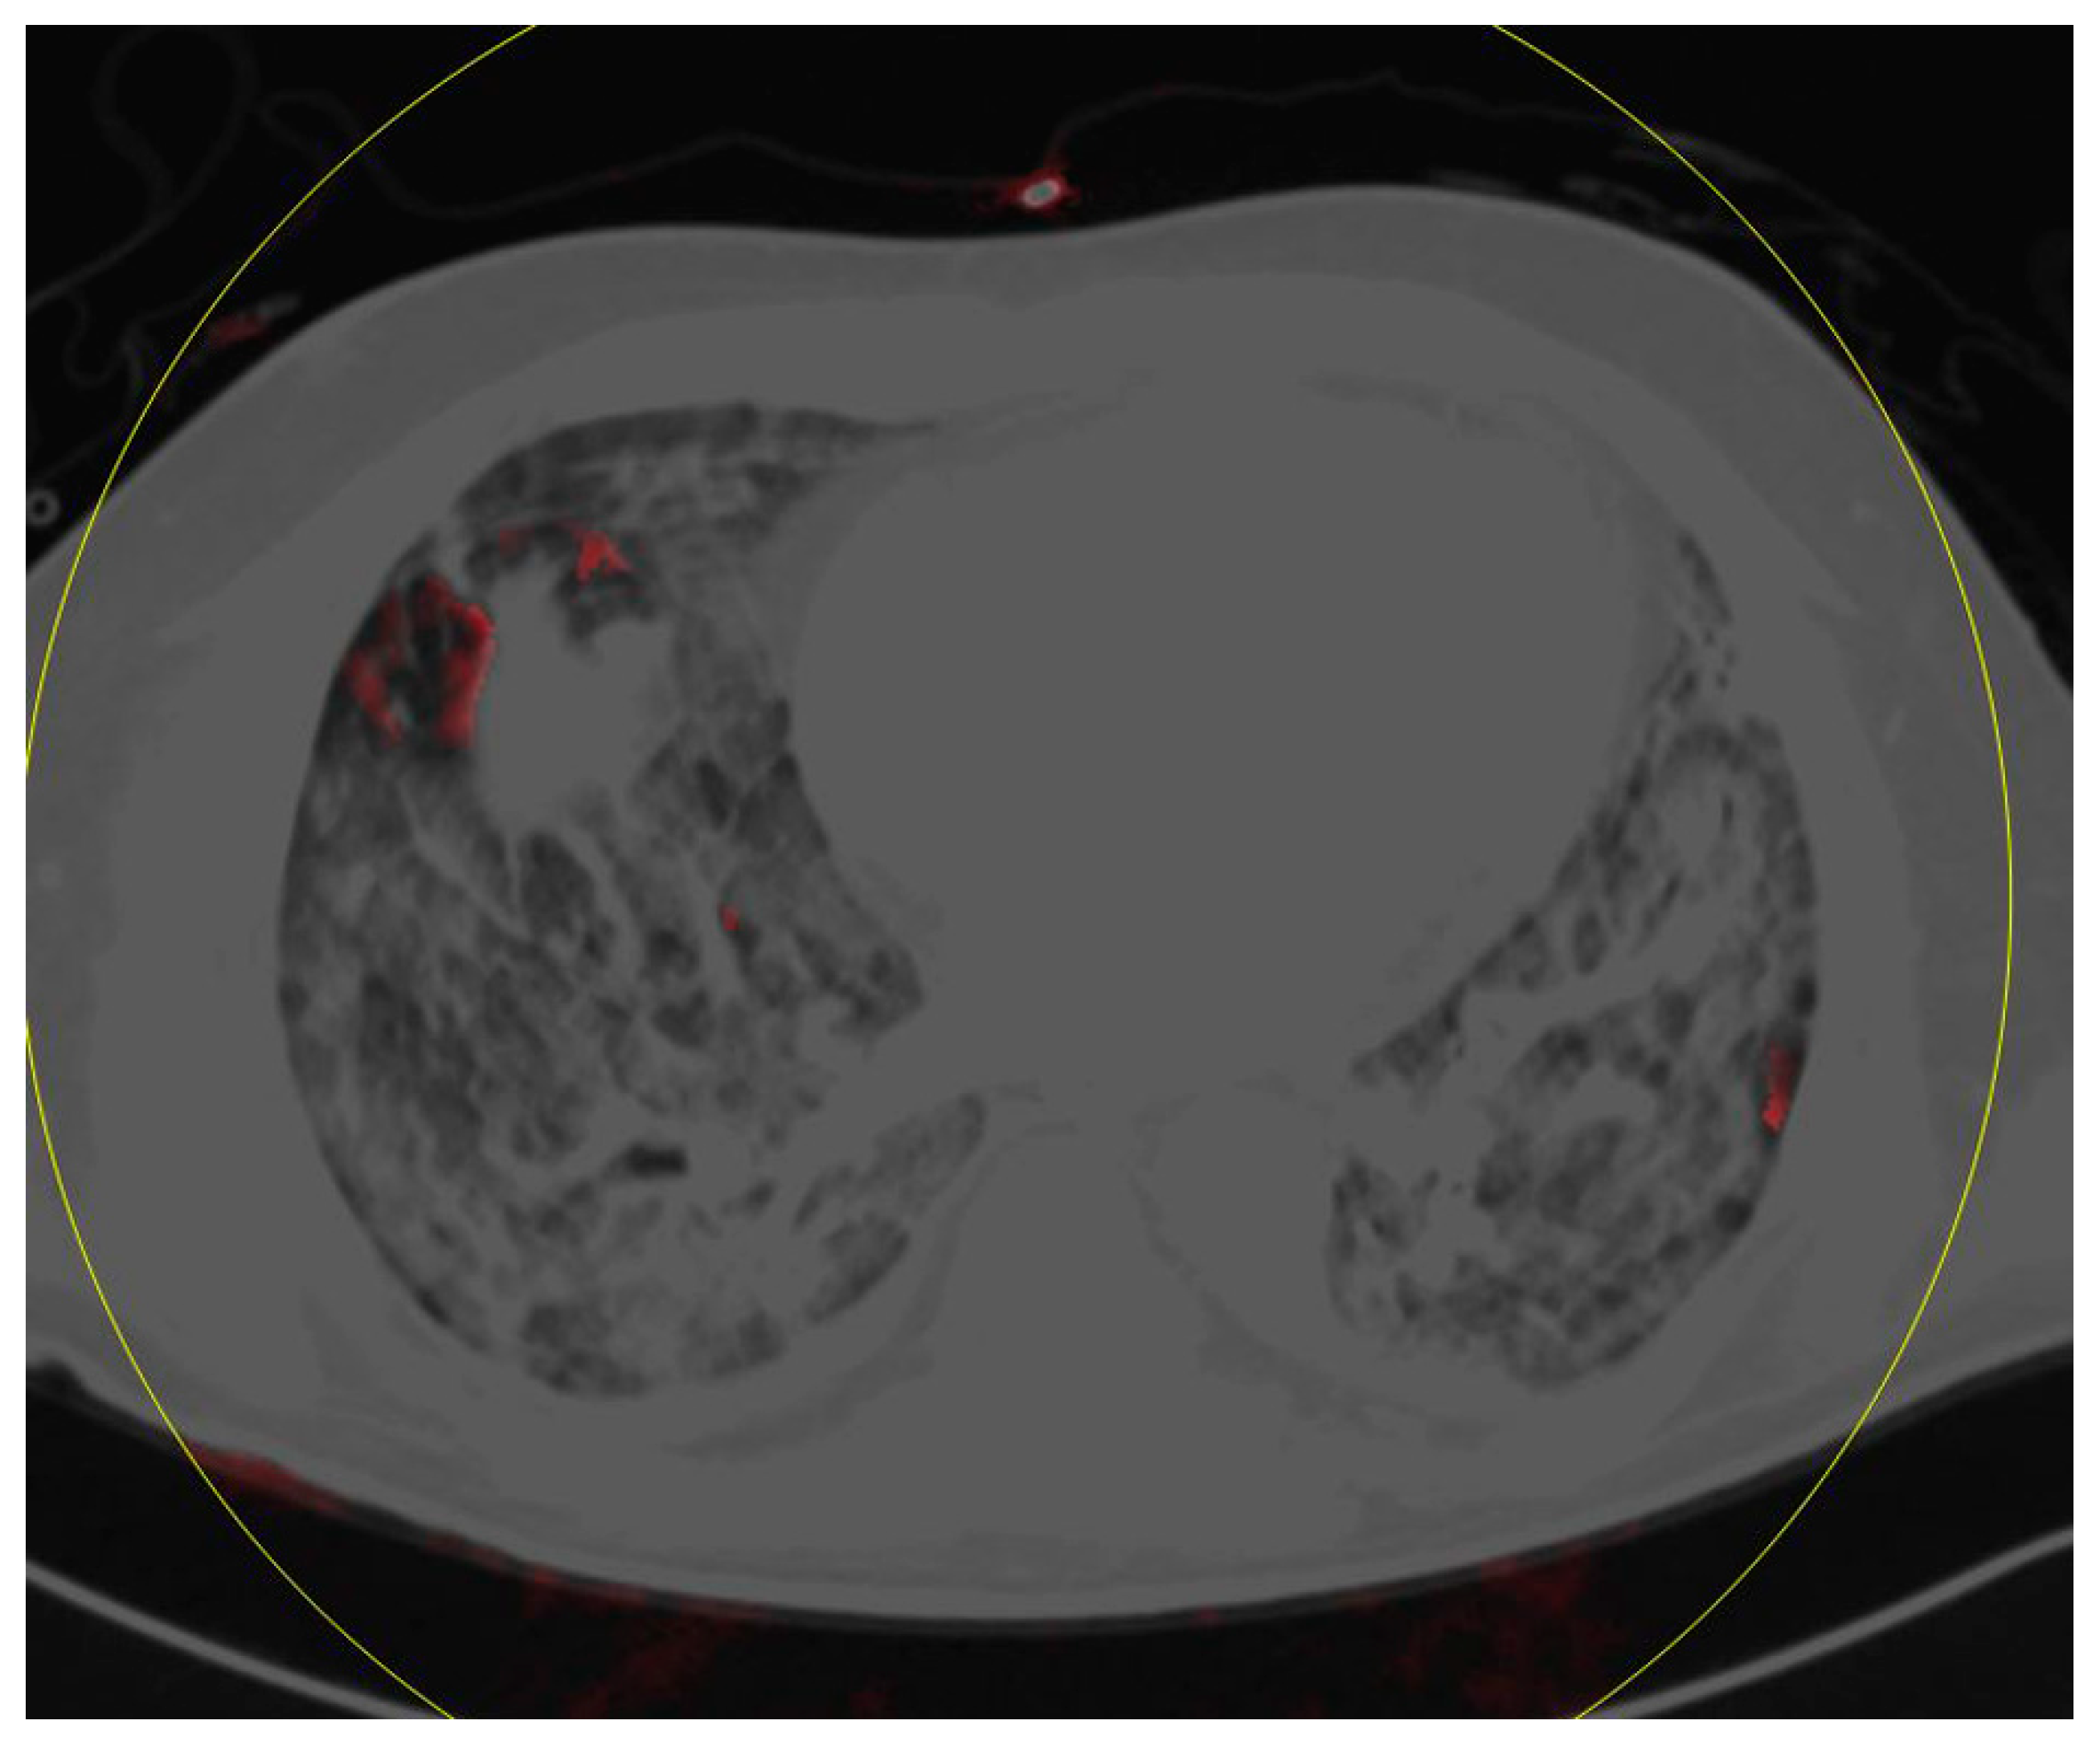

Dual-Energy Computed Tomography of the Lung in COVID-19 Patients: Mismatch of Perfusion Defects and Pulmonary Opacities

3.3. Perfusion Defects and Automatic Opacity Score Analysis

4. Discussion